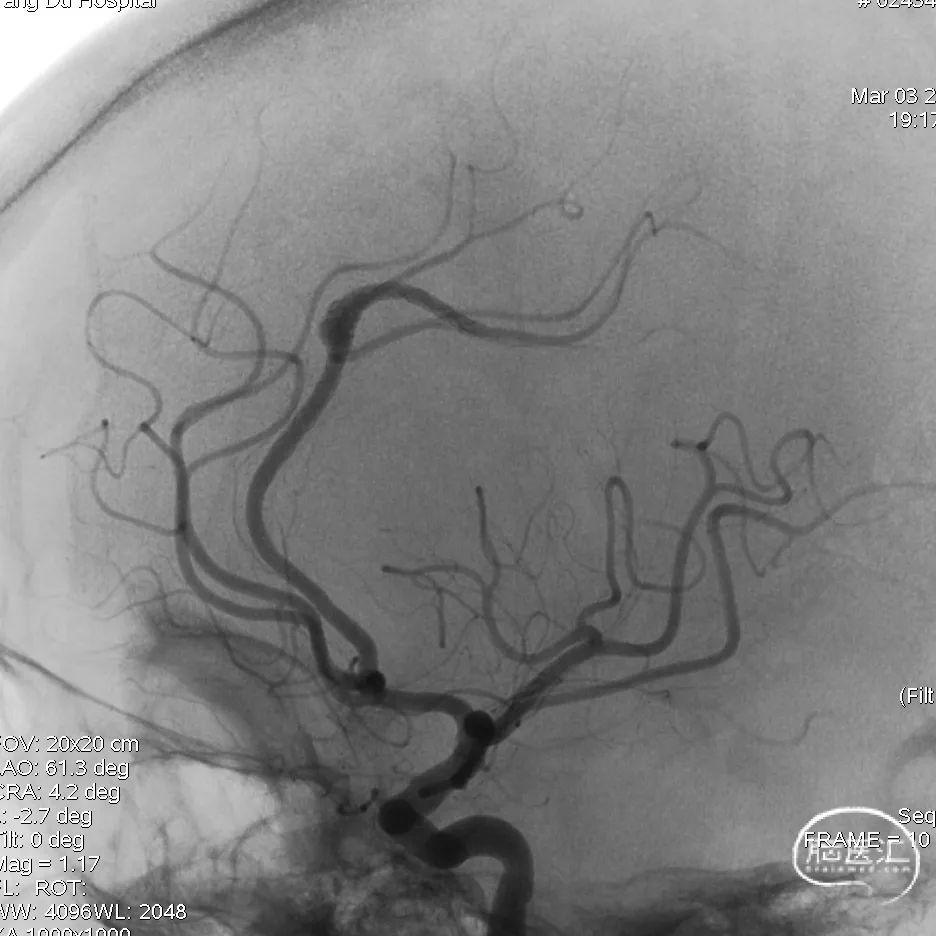

常规消毒铺巾,采用Seldinger穿刺右侧股动脉穿刺,置入8F血管鞘,进行全脑血管造影。左侧颈内动脉造影未见明显异常;右侧颈内动脉正侧位造影显示右侧颈内、大脑中动脉、大脑前动脉未见明显狭窄及闭塞;左侧椎动脉正侧位造影见左侧小脑后下动脉瘤;右侧椎动脉造影未见血管闭塞及狭窄。3D造影检查显示动脉瘤大小为0.5mm*0.45mm。

在泥鳅导丝引导下,同轴将远端通路导管输送到左椎V1段,撤出泥鳅导丝,选择工作角度后,再次入路造影。

在微导丝引导下,将血流导向密网支架专用微导管缓慢顺利通过左侧小脑后下动脉瘤,放入动脉瘤远端,撤出微导丝,再次手推造影确认真腔。

将血流导向密网支架经微导管同轴通过动脉瘤,缓慢撤微导管释放血流导向密网支架,全程放完后,再次造影确定支架内血流通畅。

再次行全脑血管造影,见血流灌注良好、通畅,退出导管。